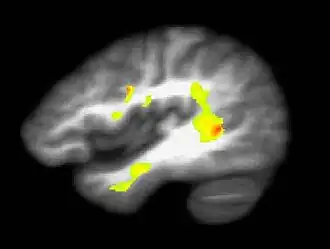

Ação da Cannabis sativa e Cannabis indica no sistema nervoso central

O delta-9 THC, após chegar ao encéfalo é absorvido por receptores específicos, as anandamidas. São encontradas altas densidades de receptores de THC no córtex cerebral, hipocampo, cerebelo e gânglios basais, o que explica os respectivos efeitos físicos e mentais associados ao consumo da droga:

Os receptores de THC localizam-se especificamente nos neurônios do sistema de opioides endógenos (Sistema relacionado a secreção de substâncias opioides pelo próprio organismo),a partir da ligação do THC com seus receptores localizados nesse sistema há uma excitação dos neurônios componentes do mesmo, que enviam sinais aos neurônios dopaminérgicos do sistema límbico (responsável principalmente pela regulação dos processos emocionais), suscitando a liberação de mais dopamina (neurotransmissor relacionado a sensação de prazer) dando sensação de prazer e euforia. A ação no sistema límbico, que além da regulação dos processos emocionais está relacionado a memória de curto prazo, também explica portanto, a "falha" de retenção desse tipo de memória. É importante ressaltar,contudo, que apesar da memória de curto prazo não estar intimamente relacionada com a aprendizagem, a memória de longo prazo, relacionada com esse fato, pode se formar a partir da memória de curto prazo , que tem a possibilidade de ser armazenada temporariamente e depois transferida para áreas relacionadas com a memória de longo prazo.

Sistema límbico e circuito de recompensa cerebral

Dentro do sistema límbico é possível identificar uma área relacionada com a sensação de prazer, inclusive o prazer sexual e o causado pelo uso de drogas, essa área é denominada circuito de recompensa cerebral O circuito começa na Área Tegmentar Ventral, segue para o Núcleo Accubens e termina no Córtex Pré-Frontal. Os neurônios que participam desse "caminho" são dopaminérgicos, todo tipo de utilização de drogas e a subsequente sensação de prazer gerada pelo uso estão,direta ou indiretamente, associadas ao circuito de recompensa cerebral, e consequentemente a quantidade de dopamina disponível na fenda sináptica (numa análise qualitativa final há sempre um aumento da quantidade de dopamina [aumento agudo], seja por inibição geral ou parcial das bombas de recaptação do neurotransmissor, ou seja pela estimulação de maior quantidade do mesmo.) É a ativação desses receptores localizados nos circuitos centrais de recompensa do cérebro que desempenham um papel importante na manutenção da autoadministração da maconha em humanos e na mediação dos efeitos ansiolíticos e agradáveis da droga.[79]